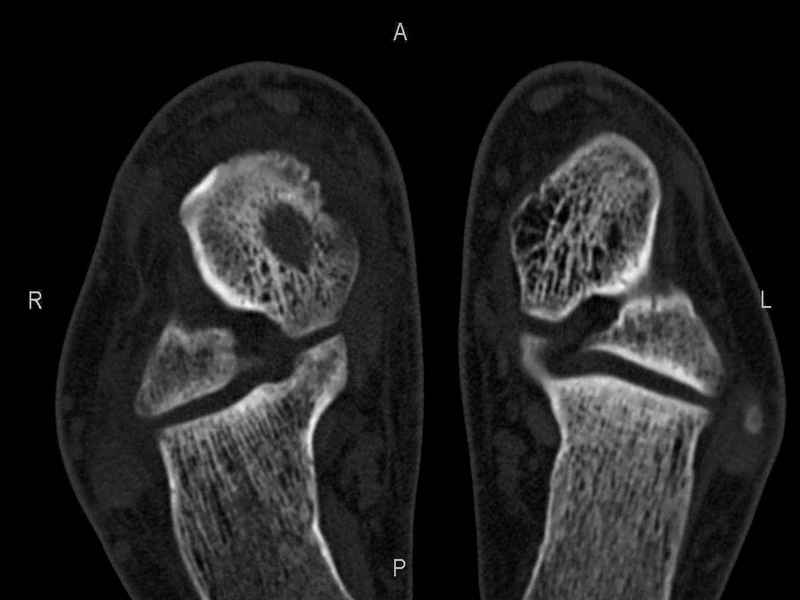

Рассекающий остеходрит + киста шейки тарана

Уважаемые коллеги, обратился за помощью пациент, мужчина, 25 лет. С жалобами на болевой синдром в области голеностопного сустава и среднем отделе стопы.

Травму отрицает. Со слов, болевой синдром в течении 1 года. Последние 1-1.5 мес периодически вынужден пользоваться костылями. После ограничения нагрузки боли уменьшаются. Соматически здоров. До появления болей активно занимался рукопашным боем.

На СКТ картина рассекающего остеохондрита блока таранной кости, киста шейки таранной кости с признаками импрессии суставной поверхности. А также - разрастания переднего края б\берцовой кости сопровождающиеся клиникой импиджмент синдрома.

Предполагаемый план лечения- удаление свободного фрагмента суставного хряща из трансмаллеолярного доступа с рассверливанием поверхности дефекта, кюретаж кисты шейки с заполнением полости биокомпозитом + дебридмент переднего отдела голеностопного сустава.